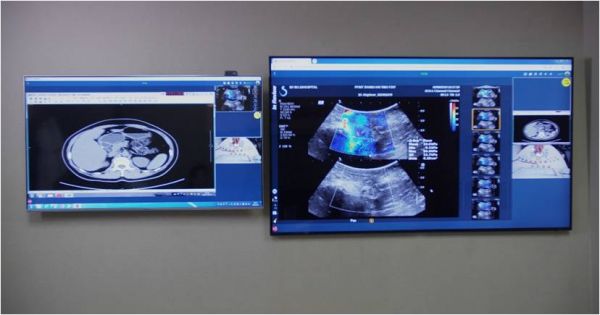

三星QLED 8K电视进驻5G超声联合创新实验室,5G+8K跨行业应用场景初现

三星作为行业内少有的兼备5G+8K应用的厂商,率先以科技附能医疗行业。三星QLED 8K电视已经进驻了由上海市第十人民医院、同济大学医学院超声医学研究所与上海移动共同组建的5G超声联合创新实验室,用于医疗场景的创新应用,为广大医疗工作者的日常工作带来更有力的保障。相比以往的4K显示器,QLED 8K电视让画面更加清晰、明亮,也让医生们能够为广大患者做出“一个更精准的诊断”。